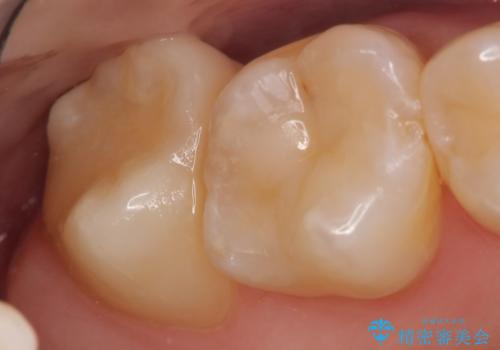

- 冷たいものを飲むと右上の奥歯がしみるので診て欲しいといらっしゃった方の症例です。

右上6番目、7番目の歯の樹脂が劣化していたため、虫歯除去後セラミックインレーによる修復を行いました。

当院のセラミックインレーはemaxという強度と審美性に優れた材料を使用しています。

またプレス方式でインレーを製作しているため、削り出しで製作するCADCAMより優れた適合性も持ち合わせており、虫歯が再発しにくい修復物です。